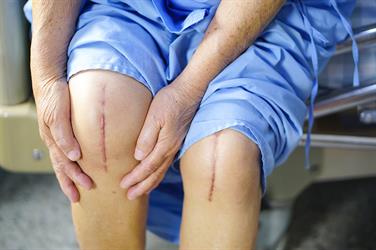

When this joint is damaged due to knee injuries, it causes severe pain that may distract the person from even simple activities such as climbing stairs or walking. The pain may even be present when sitting and sleeping.

Gradual wear of the knee joint and destruction of its articular cartilage for any reason (aging, diseases and injuries caused by trauma, etc.) causes painful movement, dryness and limited mobility of the knee joint. In this situation, by changing the joint surfaces, joint movements can be improved and pain can be eliminated.

Knee replacement surgery is one of the most common and successful orthopedic surgeries, provided that the standard prostheses of the world are used, performed by a skilled surgeon who is aware of this particular surgery and the patient has a proper rehabilitation period.

In this surgery, the damaged cartilage and bone are removed from the knee joint and replaced with an artificial joint.

The most important goal of knee replacement is to eliminate the pain that is caused in the knee due to wear and tear and arthritis, rheumatism or destruction of the joint surface. Obtaining the desired range of motion in the knee joint and correcting the deformations created in the knee are other cases of using the artificial knee joint.